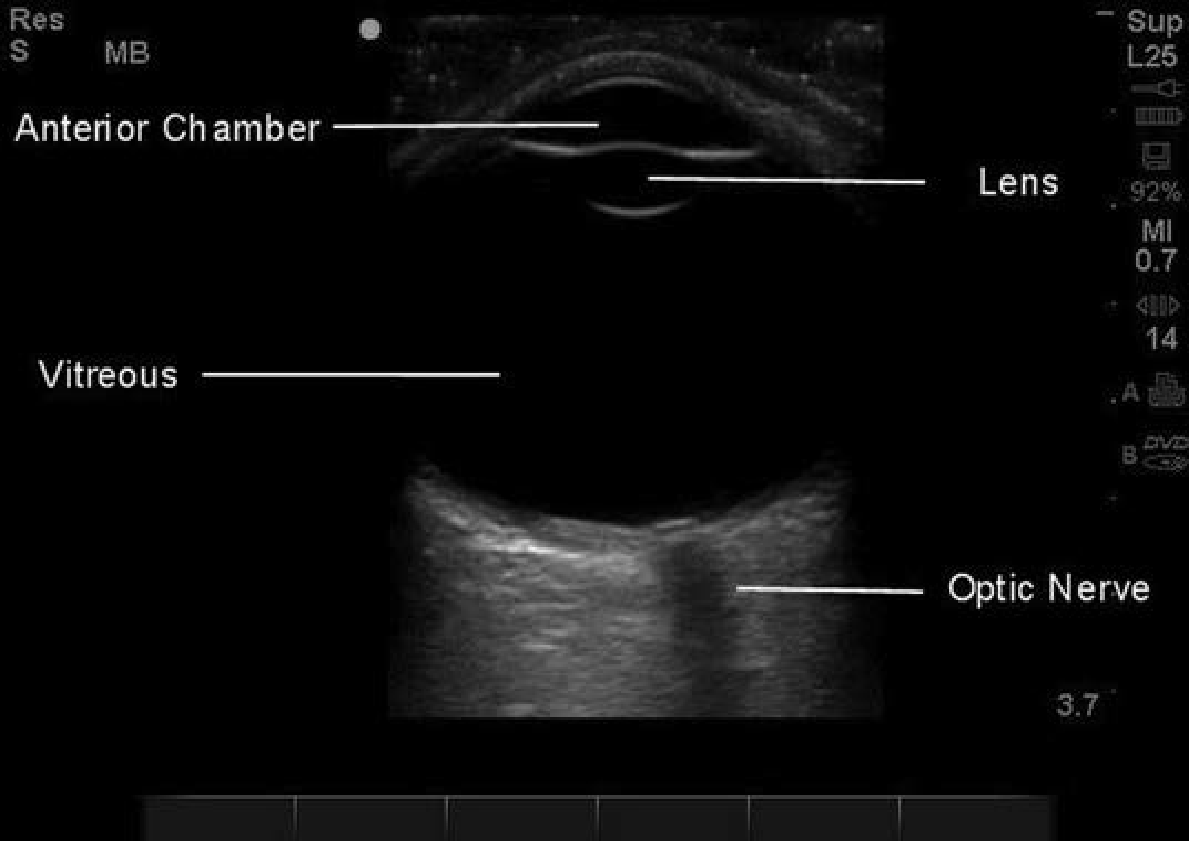

眼球超音波

• Scanning technique:linear probe,請病患閉眼往前方看,不要壓眼球,sagittal and transverse plane都要掃

• Normal anatomy of transverse view